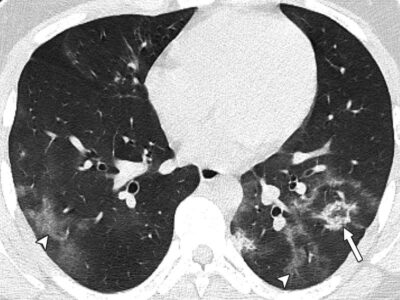

Τα μάτια αποτελούν το κεντρικότερο στοιχείο του προσώπου και συμβάλλουν σημαντικά στην έκφρασή του. Η εμφάνιση των ματιών επηρεάζεται σε ...Μαγιορκίνης: Αξονικές στους πνεύμονες ασθενών από 8 έως 18 ετών δείχνουν τις βλάβες του Covid-19

Τη δύναμη της εικόνας επιστρατεύει o επίκουρος καθηγητής Επιδημιολογίας και μέλος της Επιτροπής Εμπειρογνωμόνων Γκίκας Μαγιορκίνης, για να δείξει τις ...Αιμορροΐδες: Γιατί επιδεινώνονται στις διακοπές;